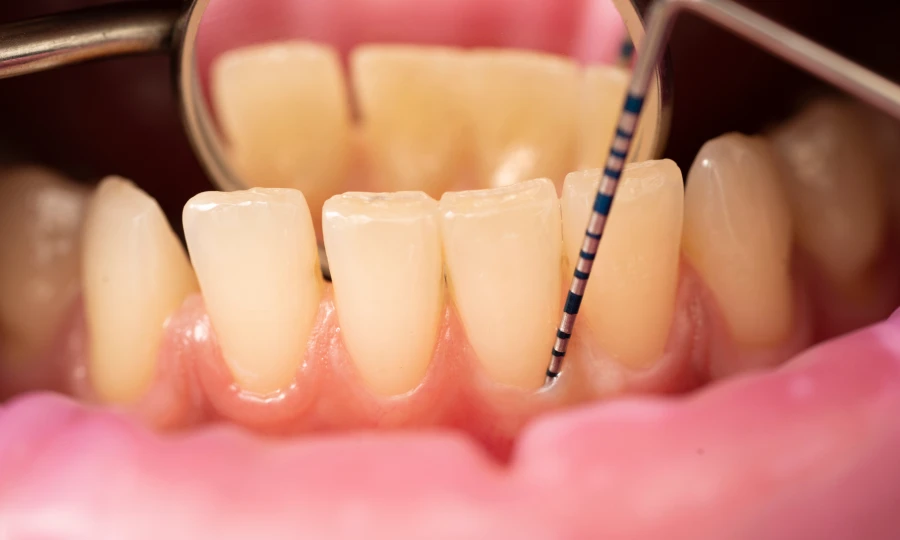

Utilisation d’une sonde parodontale

La sonde parodontale est un outil essentiel pour mesurer la profondeur des poches gingivales. Le dentiste insère doucement la sonde entre la dent et la gencive pour mesurer la profondeur de la poche. Des poches supérieures à trois millimètres peuvent indiquer une maladie parodontale.

Évaluation de la profondeur des poches

Les mesures prises avec la sonde parodontale indiquent la profondeur des poches gingivales. Des poches de quatre millimètres ou plus sont préoccupantes. Elles nécessitent une intervention pour prévenir des dommages supplémentaires.

Le dépistage précoce permet de traiter la maladie parodontale avant qu’elle ne provoque des dommages graves. Votre dentiste examinera vos gencives et utilisera une sonde parodontale pour mesurer la profondeur des poches. Une détection précoce permet d’intervenir rapidement et d’éviter la progression de la maladie.